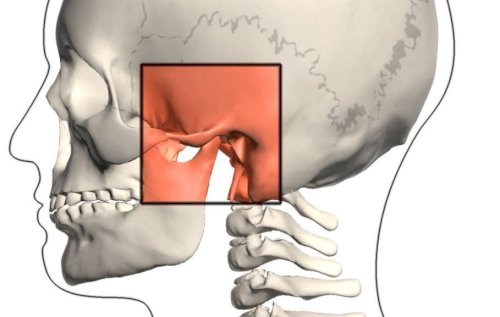

Nước giúp cho hoạt động của các cơ quan và các hệ thống cơ thể vận hành trơn tru. Nước giúp điều chỉnh thân nhiệt, loại bỏ chất thải, vận chuyển chất dinh dưỡng đến hàng tỉ tế bào trong cơ thể. Nước giúp bôi trơn chất hoạt dịch trong xương khớp, trong đó có khớp thái dương hàm – khớp nối giữa hàm dưới và hệ thống sọ mặt. Là một khớp đặc biệt và có chức năng quan trọng trong vùng hàm mặt.